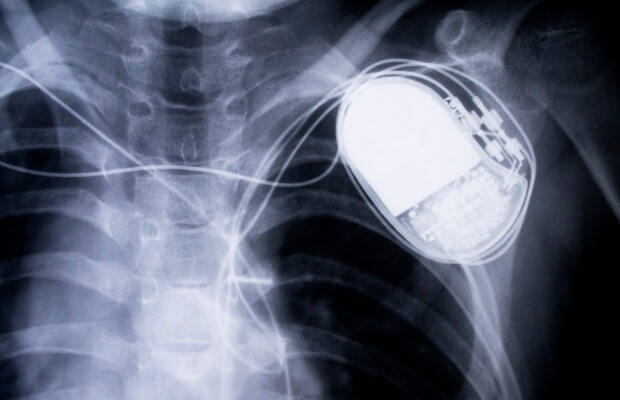

Pacemakers are small electrical devices that regulate electrical activity in the heart. Anything that produces a strong electromagnetic field can interfere with a pacemaker.

Induction hobs do generate electromagnetic fields, so keep a distance of at least 60cm (2ft) between the stovetop and your pacemaker. Most people should be able to use a hob if they follow these precautions, but if you are choosing a new cooker, it may be easier to pick one that is not an induction hob.

If in doubt, check the written information given to you when your pacemaker was inserted

Other appliances that contain a magnet include handheld hairdryers, older shavers with an electrical cord, large stereo speakers, electric toothbrushes and base chargers of ultrasonic toothbrushes. If you do use any of these, keep them 16cm (6in) away from your pacemaker. If you do get too close, don’t panic – moving further away again should mean that your pacemaker settings return to the correct level.